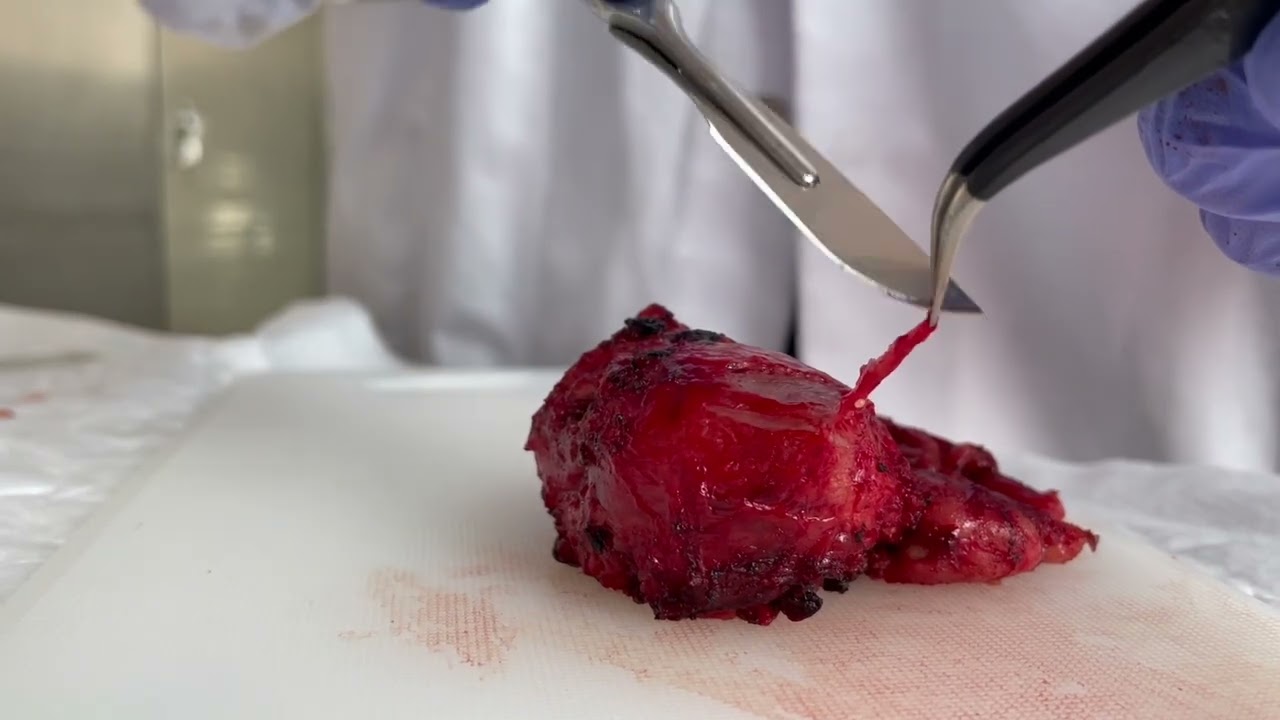

PSMA Radio Guided Surgery in Primary Prostate Cancer

Robot-assisted radioguided surgery using a DROP-IN gamma probe